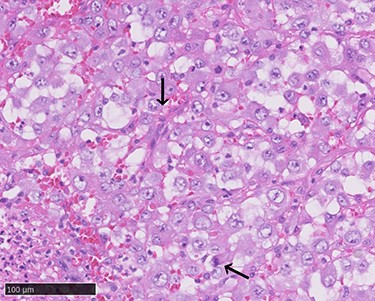

Positron emission tomography–computed tomography (CT) revealed high fluorodeoxyglucose (FDG) accumulation in her oral cavity and right shoulder in accordance with the location of the AVM (Fig. 4). High accumulation was also evident in her left lung, lumbar spine, piriformis and lymph nodes, suggesting multiple metastases. We diagnosed the masses in the oral cavity as metastatic AS, with the primary tumour located in the right shoulder, where the massive AVM was suspected to have malignantly transformed. The patient desired the best supportive care and declined additional treatments such as radiotherapy and chemotherapy. She died 4 months after initially noticing the intraoral masses. An autopsy was not performed.

Positron emission tomography–computed tomography (PET-CT). High fluorodeoxyglucose (FDG) accumulation in the oral cavity as well as in the right shoulder where the AVM was located. High accumulation was also evident in the left lung, lumbar spine, piriformis and lymph nodes.

AS is an aggressive malignant tumour with high metastatic potential. Main metastatic sites of AS include the lungs (25%), bone (22%), liver (16%) and brain (11%) (3). Intraoral metastatic AS is rare but tends to localize in the gingiva (4). As is often the case with oral metastases from other primary lesions, their presence is evidence of widespread disease. Although we could not identify the primary lesion in the right shoulder by visual inspection or CT scan due to the massive AVM, we considered it highly unlikely that the masses in the oral cavity formed the primary lesion. Only a few studies have reported on primary intraoral AS with multiple lesions, and the widest range of high FDG accumulation in our case was observed in the right shoulder.

In our case, the location of the primary lesion could not be clarified given the existence of multiple metastases at the time of diagnosis. However, it is reasonable to speculate that AS arose from the shoulder AVM, where the widest range of FDG accumulation was observed. Careful monitoring of AS occurrence is needed in patients with vascular malformation, particularly those with risk factors such as a history of radiation therapy and immunosuppression.